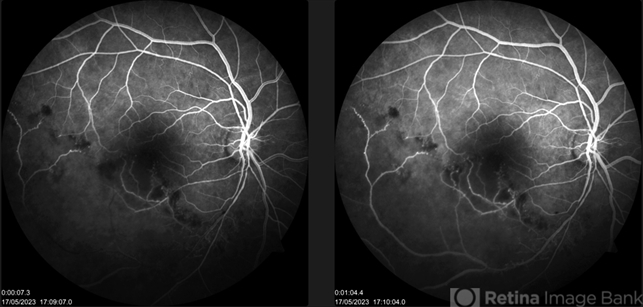

- non-perfused branch retinal vein occlusion (BRVO)

- A middle-aged man with idiopathic hypertension presented with old IT BRVO, sclerosed vein on with hemorrhages on fundus examination. FFA reveals delayed filling of vein with pruning of venules resembling buds on tree.